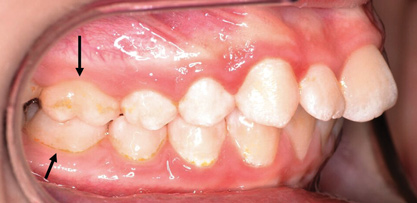

Dental impactions may occur for several reasons. A common occurrence is insufficient arch length leading to crowding. Another potential reason is early loss of primary teeth without proper space maintenance, allowing the permanent dentition to drift mesially and block out the primary tooth's successor. Maxillary canines are the most commonly impacted teeth besides third molars. These teeth have the longest path of eruption, are one of the last teeth to erupt into the mouth, easily become blocked out due to crowding or trauma history, and have a genetic component to being palatally impacted.5,6 Early signs of canine impaction may be severe crowding and the permanent lateral incisor crowns flaring distally. The crown of the impacted canine, in essence, is applying pressure to the roots of the lateral incisors in these instances (Figure 3 and Figure 4).

Fig 3. Impacted canine, dentofacial signs.

Figure 3

Fig 4. Impacted canine, radiographic signs. Lateral incisor crown distal flaring is apparent.

Figure 4